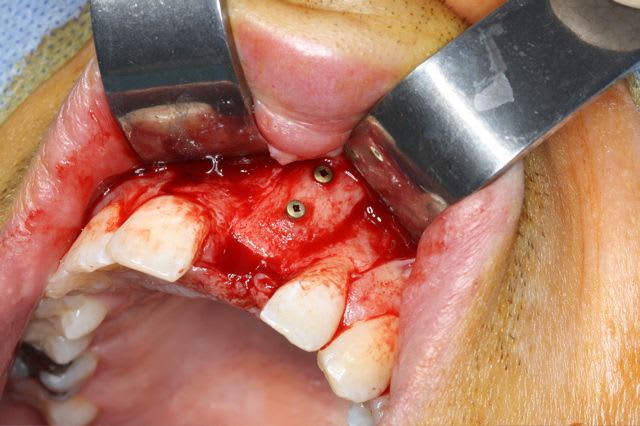

dépose des vis et pose de l'implant à 5mois1/2 avec un cj roulé et mise en place de la vis de cica,

nobel effectivement: RP Replace Groovy 4*13

Non pas speedy mais straight: apex moins agressif et implant moins compressif

J'ai eu beaucoup de craterisation avec le speedy ( surtout sur des sites anciens ) et sur une greffe je préfère la mise en place plus douce du straight pour ne pas risquer de 'décoller' le greffon cortical